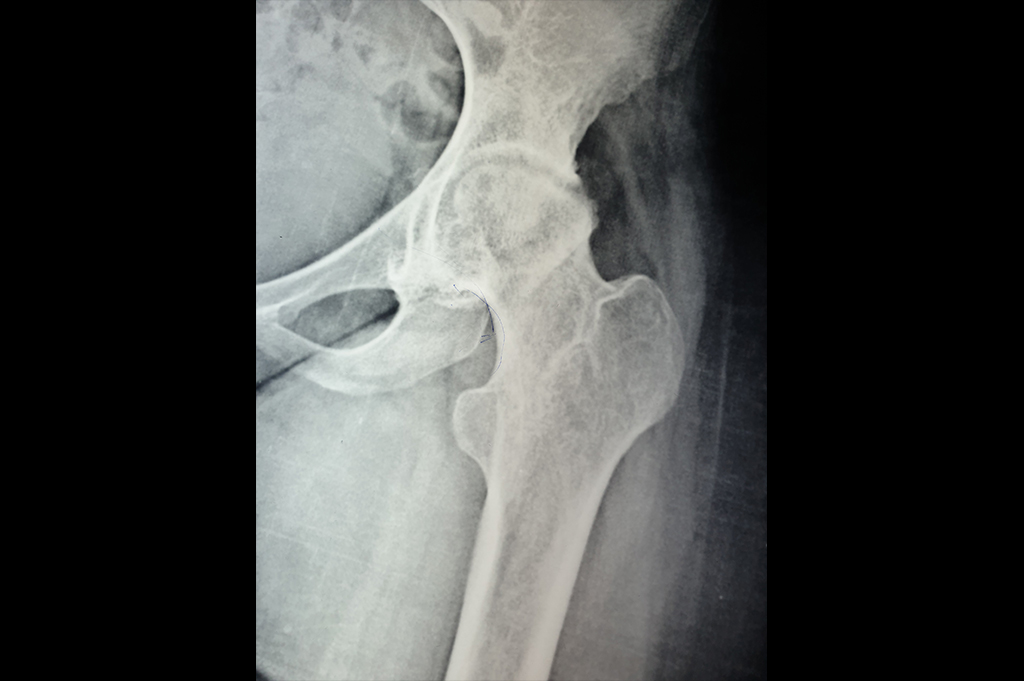

Intertrochanteric Fracture